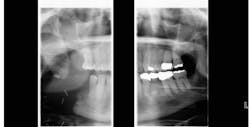

A panoramic radiograph showed the previously resected area was now fully displaced, and the musculature was causing rapid changes in the rotation of the two pieces away from each other (figure 2). The patient now had a fistula draining from the lower border of the mandible through the skin.